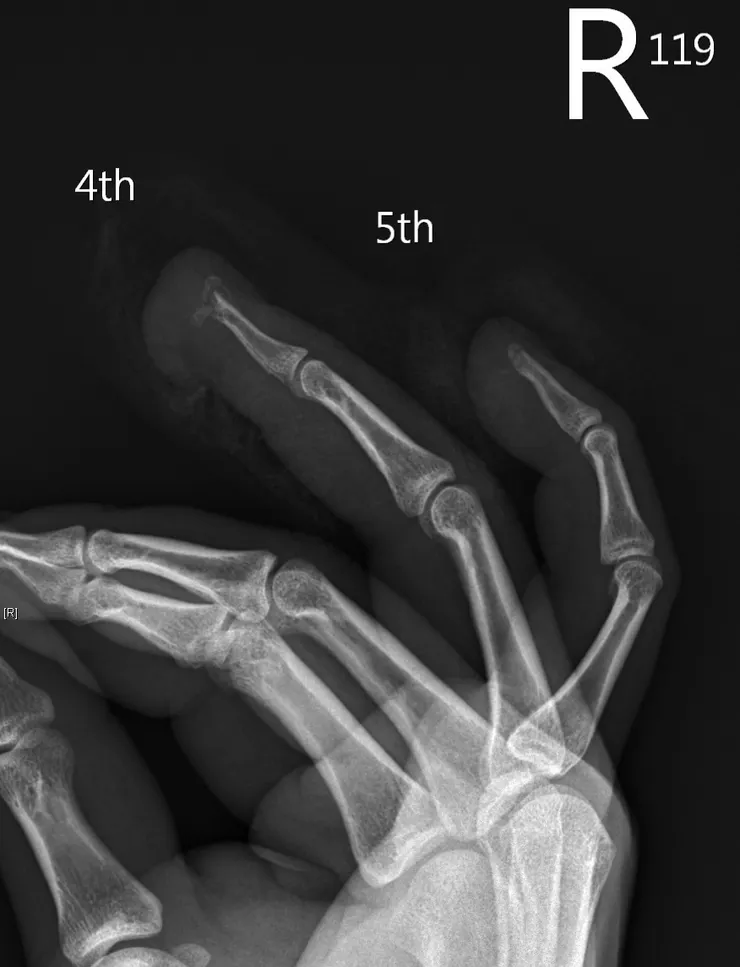

病患是一位與我年紀相仿的男性,在工作中不慎被機器壓傷被送往急診

在急診照了X光後發現有骨折,並且指頭上有個開放性傷口

在第一次門診時,手上縫了不下五針,皮膚顏色尚可,且微血管回填測試呈現陽性(capillary refilling test positive,測試皮膚是否有足夠的血液灌流)

皮膚顏色雖有些暗沉,但微血管回填測試依舊正常,看來指尖血液灌流不受影響

即使微血管回填測試沒問題,我還是懷疑在骨頭傷到的過程中,有血管的傷害

導致傷口沒辦法獲得血液來的養分,最後無法癒合